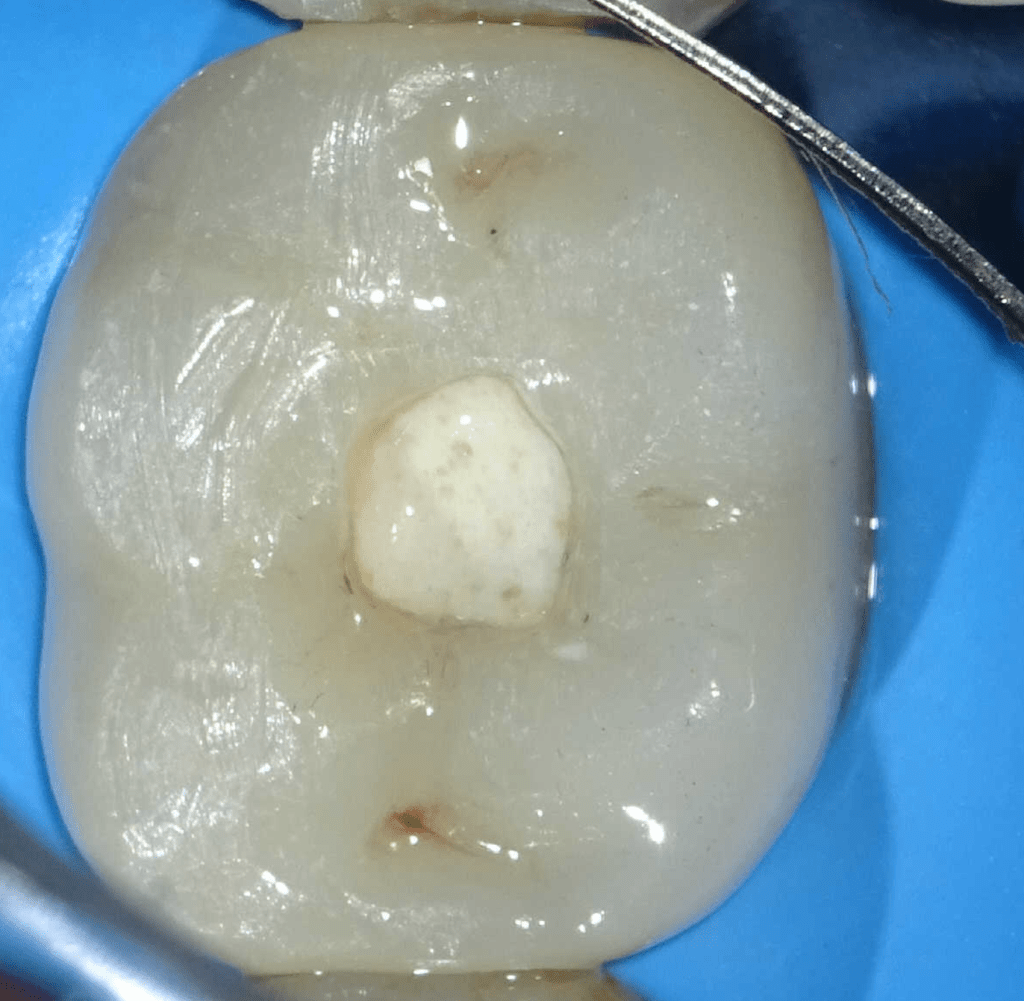

Acceso ultraconservador a través de incrustación reciente